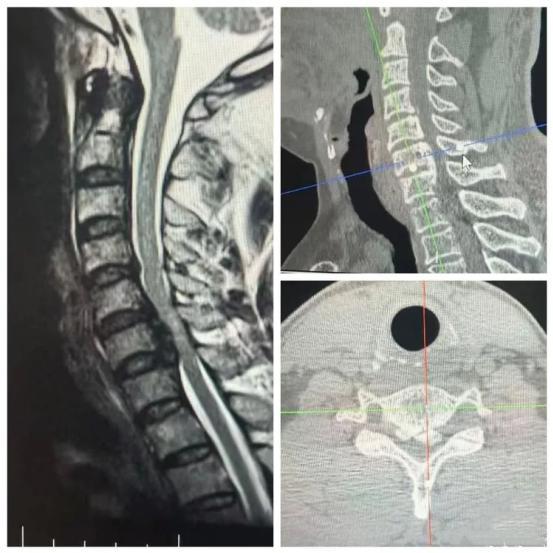

看完影像资料后,在场所有专家都不由心头一紧:钙化的后纵韧带死死顶住椎管内硬脊膜,把脊髓挤得只剩一条缝,就像一根快要被挤断的电缆,任何细微的外力都可能瞬间引发高位瘫痪。手术难度大,风险高,堪称“刀尖上行走”。

(▲术前影像学资料显示:神经根及脊髓受压严重,病情凶险)